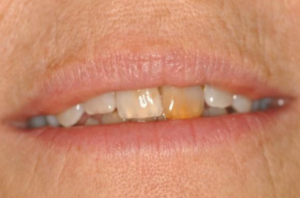

This patient came to the practice with concerns regarding the appearance of her front tooth. The tooth was traumatised as part of a childhood injury and had been compounded by an attempt to treat the tooth much later. It surprises me how people can put up with pain and discomfort for so long. This lady has had one to two years of discomfort but was reaching a point of not being able to control it. The tooth was becoming more painful, as well as preventing her from smiling. Personally, I feel that this needs immediate treatment, as pain and discomfort can have a major impact on a person’s quality of life. A huge part of our job in dentistry is to help people, relieving pain and discomfort and wherever possible, give a good functional and aesthetic result. This topic will be covered in a future article.

The patient presented to Dr. Tom with an over-erupted, discoloured upper left central incisor. She has a high lip line and all her front teeth and gums show with her smile. The patient had previously been informed that the pulp chamber and canal had become calcified. Her dentist had tried to find the canal but, unfortunately, had perforated through the buccal surface of the root subgingival. This has resulted in infection. At this time, I knew it was going to become very interesting and I was curious as to what could be done.